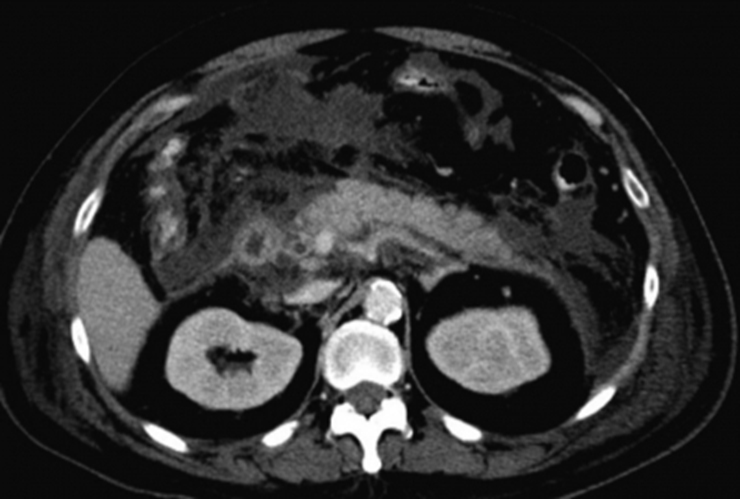

66歳の男性。総胆管結石の加療目的で入院となり,内視鏡的結石除去術を施行した。終了2時間後から持続性の心窩部痛と背部痛を訴えた。体温37.5℃。脈拍108/分,整。血圧94/66mmHg。呼吸数24/分。SpO2 94%(room air)。腹部は平坦で,心窩部を中心に広範囲に圧痛を認める。血液所見:赤血球502万,Hb 15.3g/dL,Ht 45%,白血球12,700,血小板26万,PT-INR 1.1(基準0.9~1.1)。血液生化学所見:総ビリルビン4.4mg/dL,AST 370U/L,ALT 177U/L,LD 491U/L(基準176~353),γ-GTP 337U/L(基準8~50),アミラーゼ 1,288U/L(基準37~160),尿素窒素23mg/dL,クレアチニン1.2mg/dL。CRP 9.3mg/dL。腹部造影CTを別に示す。